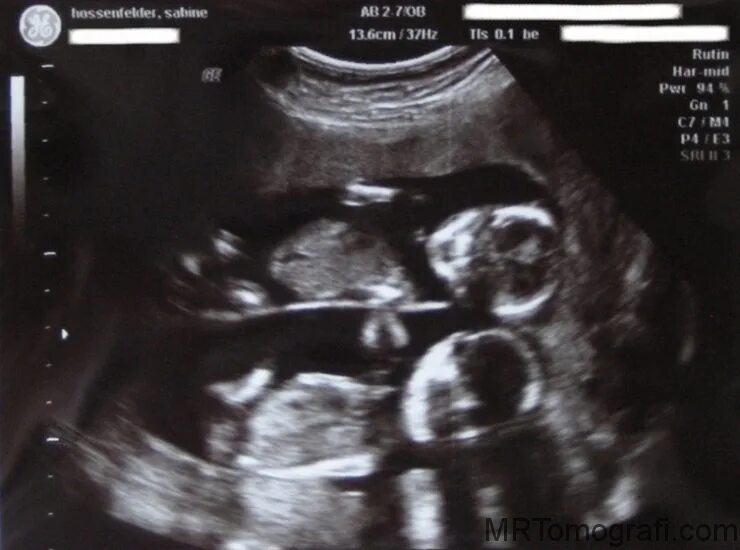

27 недель беременности двойня